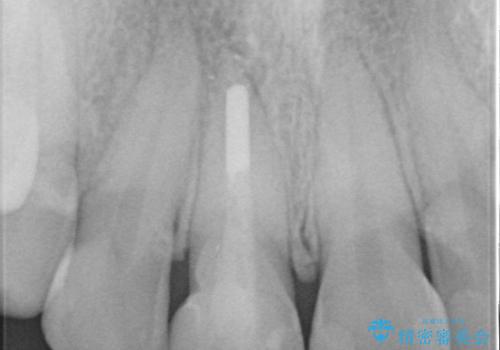

- 前歯のガタつき、変色を主訴に来院された患者様です。術前診査のCT撮影にて、変色した前歯の根の先に病巣があることが判明しました。そこで、マウスピースによる矯正治療と、前歯の根管治療、かぶせ物のやり直し治療を並行して行いました。